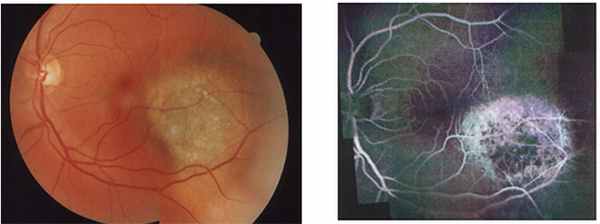

3. Флюоресцентная ангиография – метод позволяет исследовать сосуды глазного дна и выявить характерные признаки для опухолей. При этом проводится введение специального вещества (например, флюоресцеин) в вену пациента. Метод противопоказан при аллергических реакциях в анамнезе (на йод и другие медикаменты).

Горшков И.М. представил результаты комбинированной схемы лечения пациентов с меланомой хориоидеи после эндорезекции опухоли, предложив собственный подход. Эндорезекция в ряде случаев может быть альтернативой энуклеации при лечении «больших» меланом хориоидеи (Рис.3). Несмотря на то, что данный способ лечения предполагает, как правило, повторные хирургические вмешательства, несомненным его преимуществом является реальная возможность сохранения глаза и зрительных функций.

Амирян А.Г. считает, что анти-VEGF терапия лучевых осложнений после брахитерапии увеальных меланом может быть использована с целью уменьшения постлучевой экссудативной реакции (рис. 5), а также в комплексном лечении постлучевых осложнений неоваскулярного генеза (рис. 6), что в ряде случаев позволит избежать удаления глаза. Анти-VEGF терапию следует проводить в случаях стабилизации опухолевого процесса на глазном дне с формированием плотного аваскулярного очага.